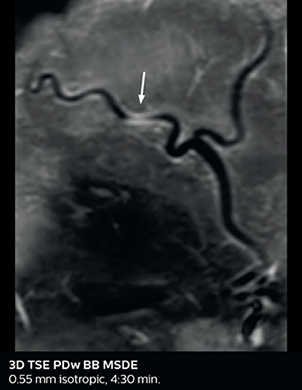

So, what is the actual impact of having more information and more diagnostic confidence? According to Dr. Savatovsky, “One of the indications I’ve seen where using Elition is most impactful is in patients with suspected giant cell arteritis. As an ophthalmologic hospital, we see many patients with suspected giant cell arteritis. Usually we were performing MRI to help us rule out an ischemic stroke, and to verify that the supra aortic vessels are undamaged. With Elition, we still do this, but now we can add on more detailed high-resolution black-blood sequences on superficial arteries. This provides us with high confidence levels for diagnosis of giant cell arteritis (GCA) and as a result, some patients are not sent for a biopsy anymore. A patient who has a normal MRI will not require a biopsy and can be discharged from the hospital in the same day. Before, such a patient would have to stay for about a week, just to find that their biopsy results were negative. We have at least three or four patients a week with suspected giant cell arteritis. For a great deal of these patients we can have a direct impact on their hospital stay.”

The 3D TSE T1w black blood MSDE sequence with fat suppression has an isotropic 0.8 mm voxel size and sagittal oblique and axial reformats are made. The images show superficial temporal artery thickening and peri-arterial fat infiltration. The 3D TSE PDw black blood MSDE with fat suppression has 0.55 mm isotropic voxels. The images shows focal involvement of the frontal branch of the superficial temporal artery.